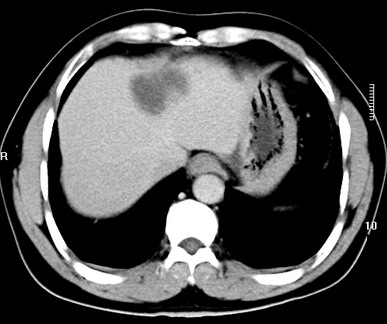

标题: CT19720:肝右叶血管瘤。肝左叶内侧段病灶考虑什么? [打印本页]

标题: CT19720:肝右叶血管瘤。肝左叶内侧段病灶考虑什么?

男,48岁,肝区不适月余,伴隐痛。

支持右叶血管瘤,左叶病灶考虑肝腺瘤。

1)不排除肝左叶肝癌。2)肝右叶血管瘤。

肝左叶炎性病变,肝癌待排。2)肝右叶血管瘤。

1.肝右叶血管瘤;2.肝左叶炎性假瘤?肝癌?建议穿刺活检.

右叶病灶典型,左叶病变慢性炎块

1、肝右叶血管瘤(典型)。

2、肝左叶病灶,强化不明显,疑炎性假瘤,建议结合临床并密切随访。

1、肝左叶炎性病变,肝癌待排。

2、肝右叶血管瘤。

肝左叶脓肿,肝癌待排。2)肝右叶血管瘤